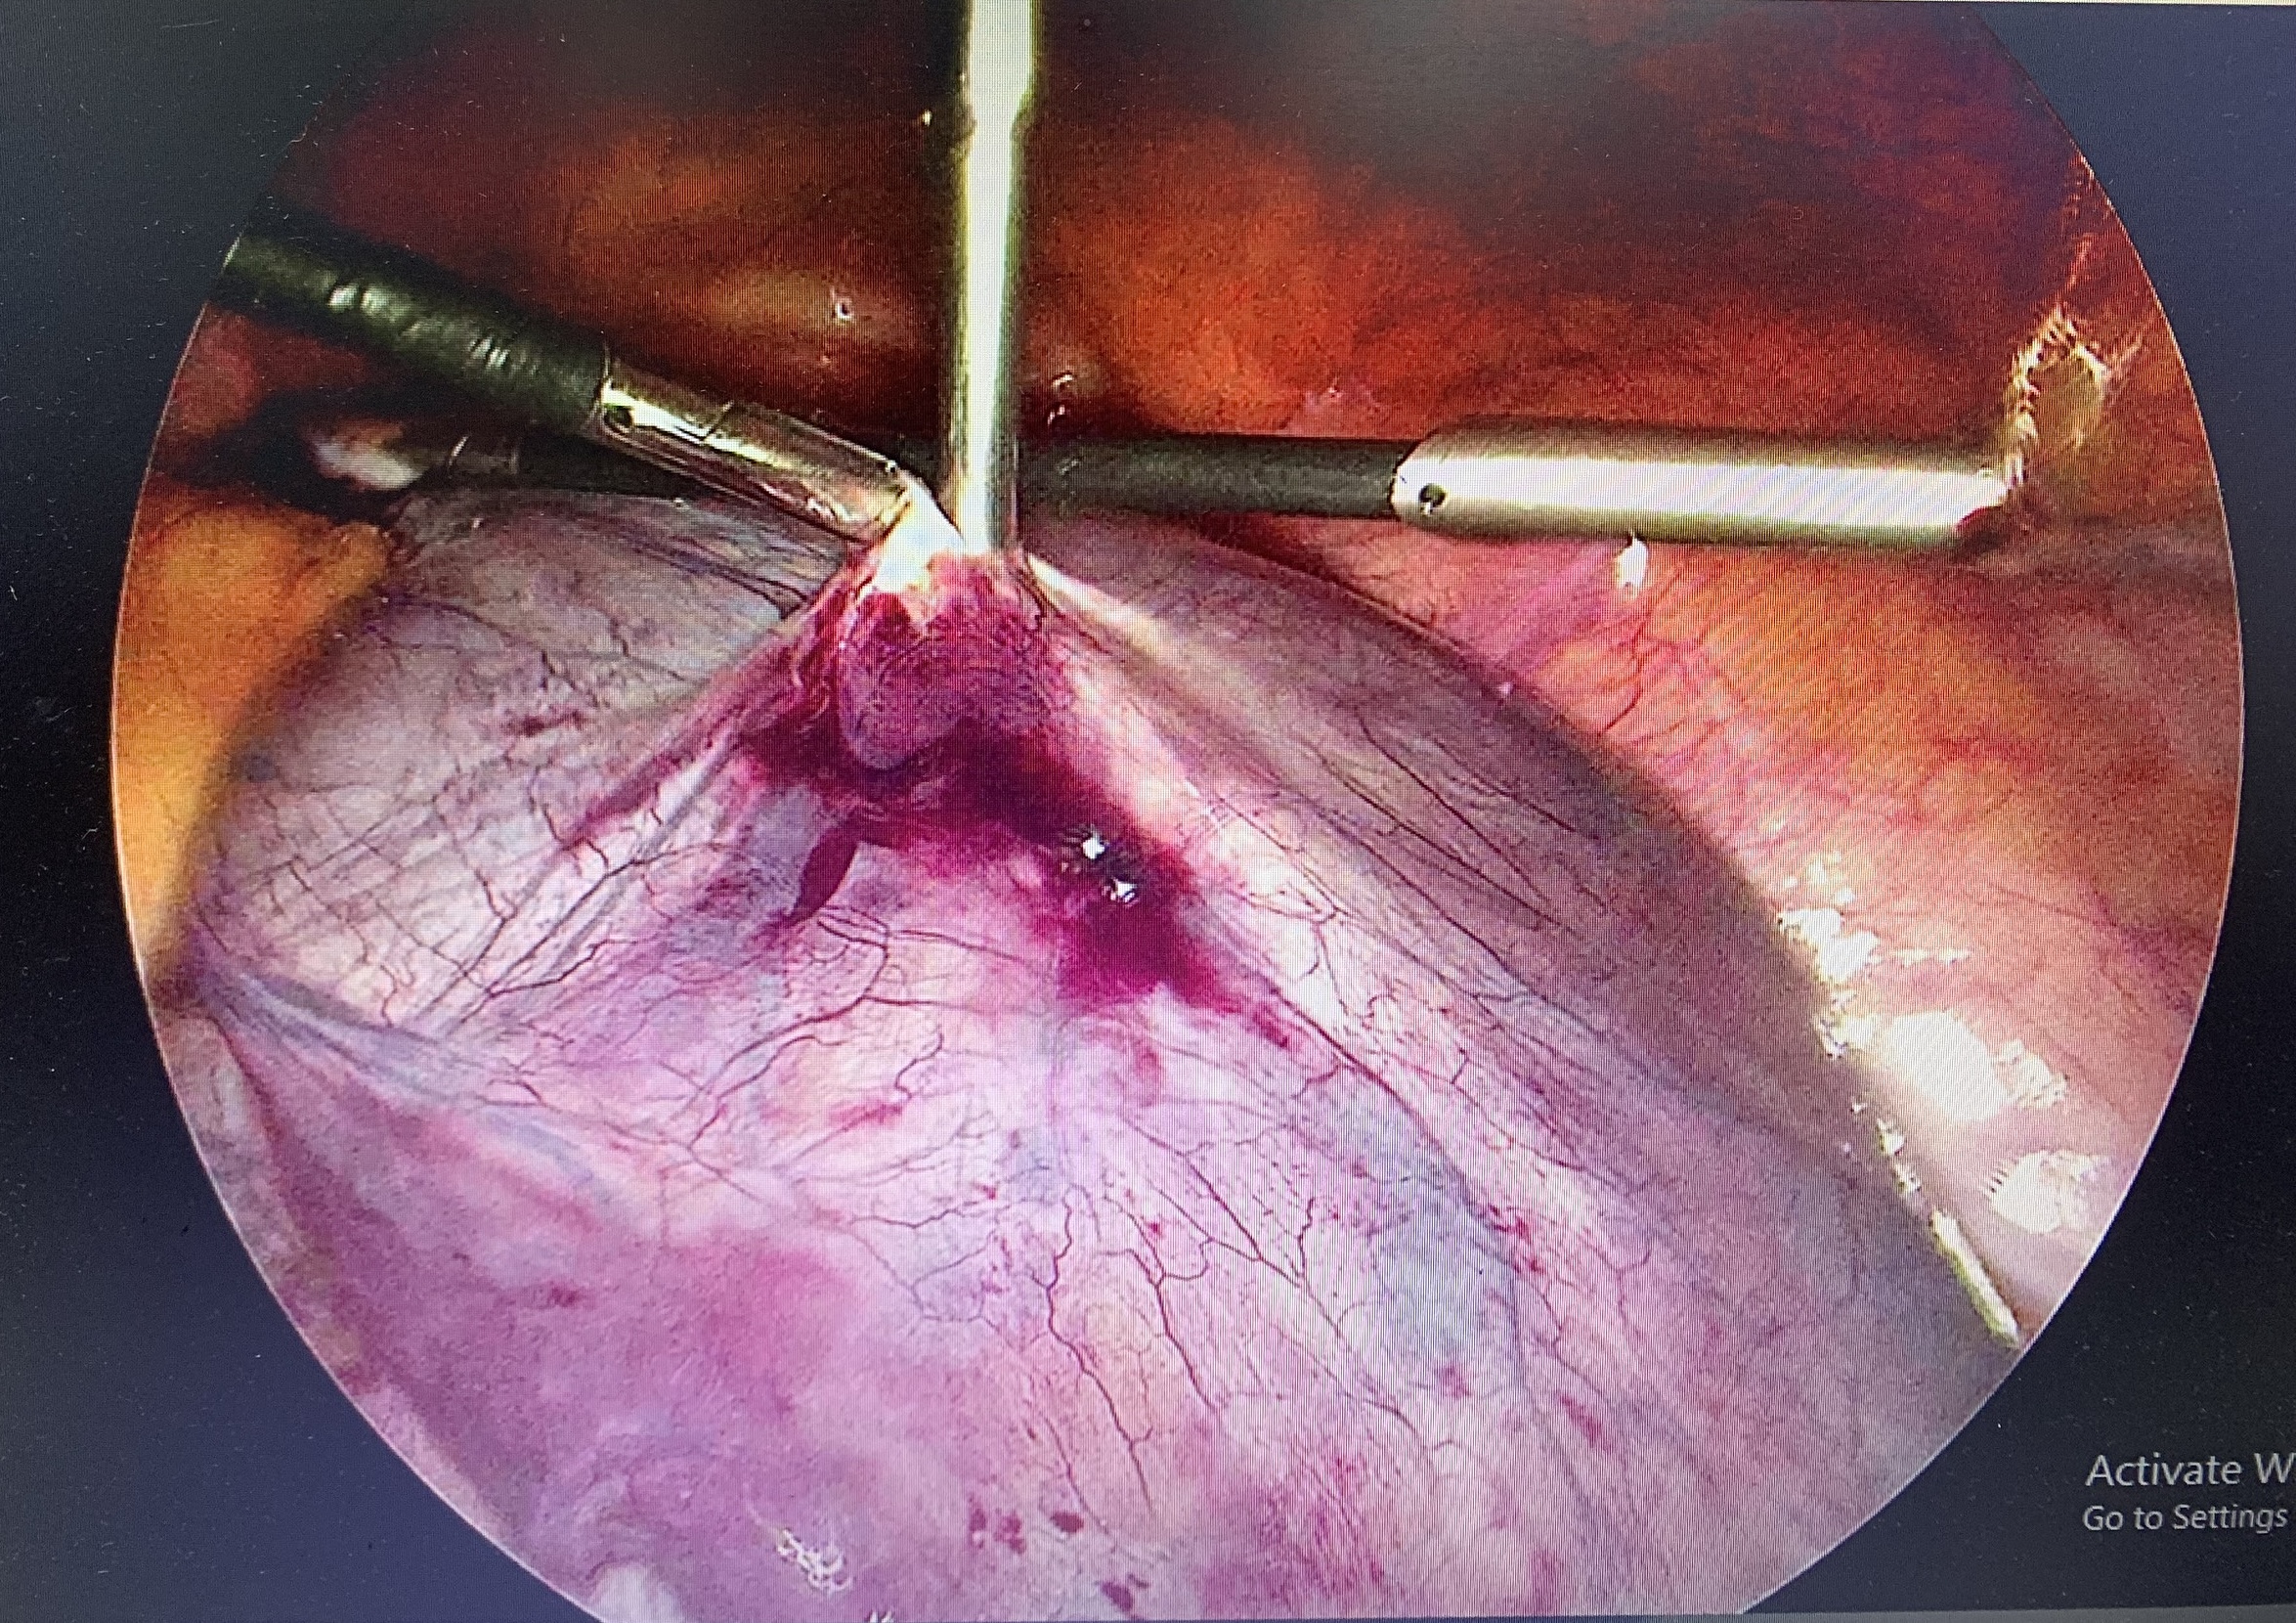

Endoscopic image of the twisted right ovarian cyst removal

The surgery was performed by the team led by Specialist doctor level 2 Hoang Thi Kim Ngan, Head of the Obstetrics and Gynecology Department at Yen Binh General Hospital. After five days of postoperative care, Ms. D’s health stabilized.